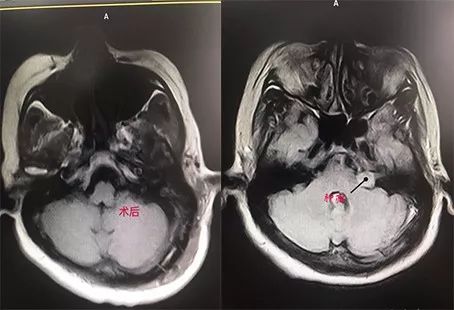

1、桥小脑角区病损切除:

3、动脉瘤夹闭: